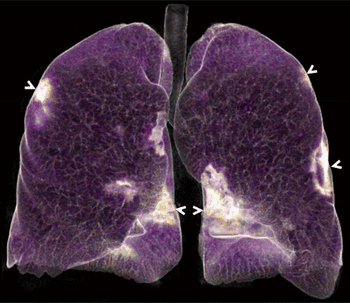

Percentage of lung opacities can be used to rate the severity of disease.

CT scan and video reveal peripheral, multilobar areas of ground-glass opacity.